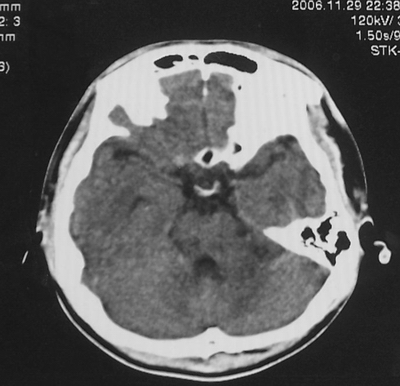

增强后

患者、男、18y,头痛5天入院。

左小脑、右丘脑区低密度影,无明显强化及占位表现,男18y,先考虑脑部炎性病变,如脑炎、血行播散性感染等,建议结合临床如脑脊液检验。

单独看左侧小脑半球的不规则形囊性低密度灶,从发病部位、年龄以及无强化、无占位效应的特点可以考虑毛细胞瘤型星形细胞瘤。同样,如果单独看右侧丘脑的近圆形低密度,也可以考虑囊变形星形细胞瘤。只是胶质细胞瘤一般为单发直接浸润、蔓延生长,而不是在脑内同时出现多个病灶,且瘤周没有一点儿水肿,暂时不予以考虑。

同时,现在已经进入冬天,一氧化碳中毒也需要考虑进去。不知道增强是什么时间做的,与平扫间隔几天?如果中间时间比较久而且进行吸氧等治疗,则平扫所示右侧颞叶密度比较低、右侧小脑半球以及脑桥也似有片囊状低密度,但在增强却没有发现就可以比较合理的解释了。